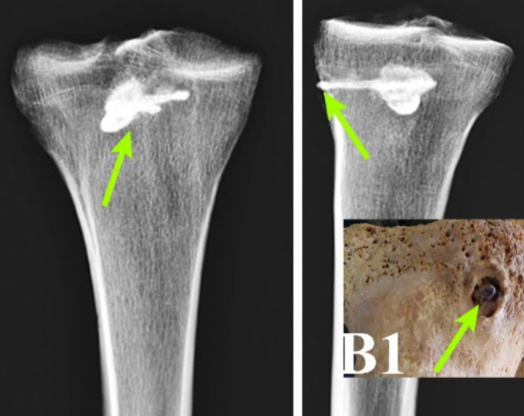

Araştırma ekibi, iskelet üzerinde BT taramaları ve X-ışını analizleri gibi modern teknolojiler kullandı. Yapılan incelemeler, savaşçının sağ kaval kemiğinin derinliklerine saplanmış, 44 mm uzunluğunda üç bıçaklı metal bir ok ucu olduğunu ortaya çıkardı.

Kemik üzerinde yapılan analizler, ok ucunun etrafında belirgin bir iyileşme olduğunu gösterdi. Yabancı cismin çevresinde yoğun kemik dokusunun oluşması, savaşçının bu ölümcül yarayı atlattığını ve sonrasında uzun bir süre daha yaşadığını kanıtladı.

Guilan Üniversitesi'nden Dr. Muhammed Rıza Eğdami, bulguları, "Kirişin etrafındaki kemik yapısında iyileşme belirtileri görülüyor ve yaranın dış durumu, önemli bir zaman geçtiğini ve iyileşme sürecinin gerçekleştiğini gösteriyor" sözleriyle açıkladı.